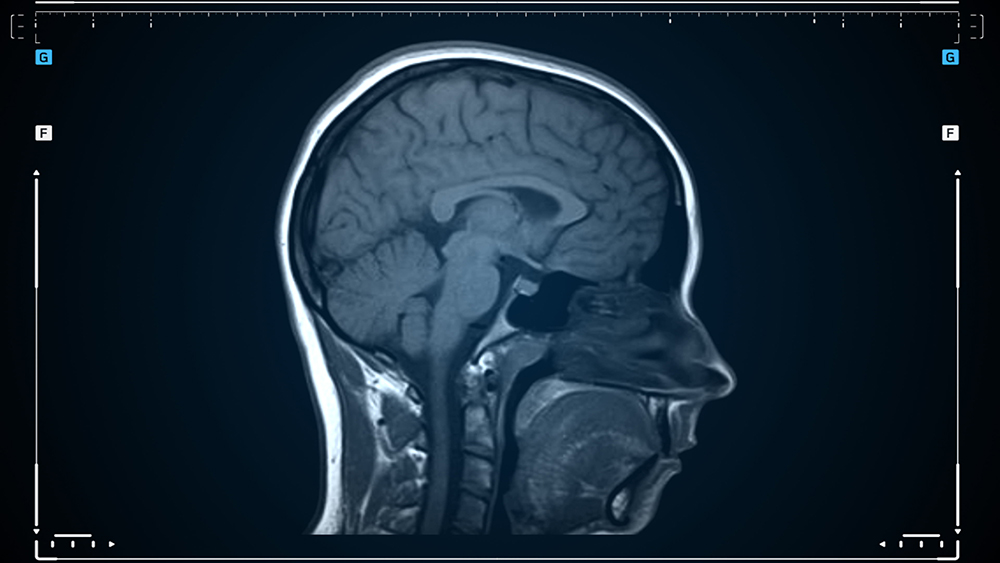

- MRI 및 MRA: 뇌혈관의 구조와 혈류를 확인하기 위한 주요 영상 진단 방법입니다.

- 뇌혈관 조영술: 모야모야병의 확진을 위해 가장 효과적인 검사로, 뇌혈관의 비정상적인 모양을 정확히 확인할 수 있습니다.

- SPECT 검사: 뇌혈류 상태를 확인하며, 병의 진행 정도를 파악할 수 있습니다.